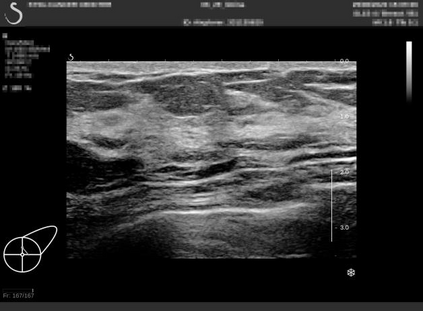

Ultrasonography is an important routine examination for breast cancer diagnosis, due to its non-invasive, radiation-free and low-cost properties. However, it is still not the first-line screening test for breast cancer due to its inherent limitations. It would be a tremendous success if we can precisely diagnose breast cancer by breast ultrasound images (BUS). Many learning-based computer-aided diagnostic methods have been proposed to achieve breast cancer diagnosis/lesion classification. However, most of them require a pre-define ROI and then classify the lesion inside the ROI. Conventional classification backbones, such as VGG16 and ResNet50, can achieve promising classification results with no ROI requirement. But these models lack interpretability, thus restricting their use in clinical practice. In this study, we propose a novel ROI-free model for breast cancer diagnosis in ultrasound images with interpretable feature representations. We leverage the anatomical prior knowledge that malignant and benign tumors have different spatial relationships between different tissue layers, and propose a HoVer-Transformer to formulate this prior knowledge. The proposed HoVer-Trans block extracts the inter- and intra-layer spatial information horizontally and vertically. We conduct and release an open dataset GDPH&GYFYY for breast cancer diagnosis in BUS. The proposed model is evaluated in three datasets by comparing with four CNN-based models and two vision transformer models via a five-fold cross validation. It achieves state-of-the-art classification performance with the best model interpretability.

翻译:超声波分析是乳腺癌诊断的一个重要常规检查,原因是其非侵入性、无辐射和低成本的特性。然而,由于其内在局限性,它仍不是乳腺癌的第一线筛选测试。如果我们能够精确地通过乳房超声图像诊断乳腺癌(BUS),它将是一个巨大的成功。我们提出了许多基于学习的计算机辅助诊断方法,以实现乳腺癌诊断/感官分类。然而,其中多数方法需要事先确定性能模型,然后对ROI内部的跨值进行分类。常规分类支柱,如VGG16和ResNet50等,可以在没有ROI要求的情况下实现有希望的分类结果。但是这些模型缺乏可解释性,从而限制了其在临床实践中的使用。在本研究中,我们提出了一个新的无乳腺癌诊断模型,在超声波图像中进行解释性特征描述。我们利用了先前的解剖学学学知识,即恶性肿瘤和良性肿瘤模型在不同组织层之间有着不同的空间关系,并提议采用状态解析法来编制这一先前的知识。拟议中的HOVer-Trans-Trading-Tradef-trainal Ex-deal-dealal-deal-deal-deal-degraphal-deal-deal-deal-deal-deal-deal disal disal-dal-dal-dal-dal-dal-deal-deal-dal-deal-deal-deal-dal-dal-dal-dal-dal-dal-dal-dal-dal-dal-dal-dal-dal-dal-I-dal-Iversal-dal-Ial-d-d-I-d-d-I-I-I-I-I-I-I-I-I-I-I-I-I-I-I-I-I-I-I-I-I-I-I-I-I-Ial-I-Ial-Ial-I-I-I-I-I-I-I-I-I-I-I-I-I-I-I-I-I-I-I-I-I-I-I-I-I-I-I-I-I-I-I-I-